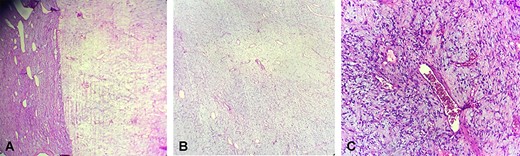

Immunohistochemical study revealed that the tumor cells were positive for estrogen and progesterone receptors, CD34 (Fig. 3a) and desmin (Fig. 3b). There were negative for smooth muscle actin and PS-100.

Positive staining with CD34 (a), desmin (b), progesterone receptor (c), estrogen receptor (d)